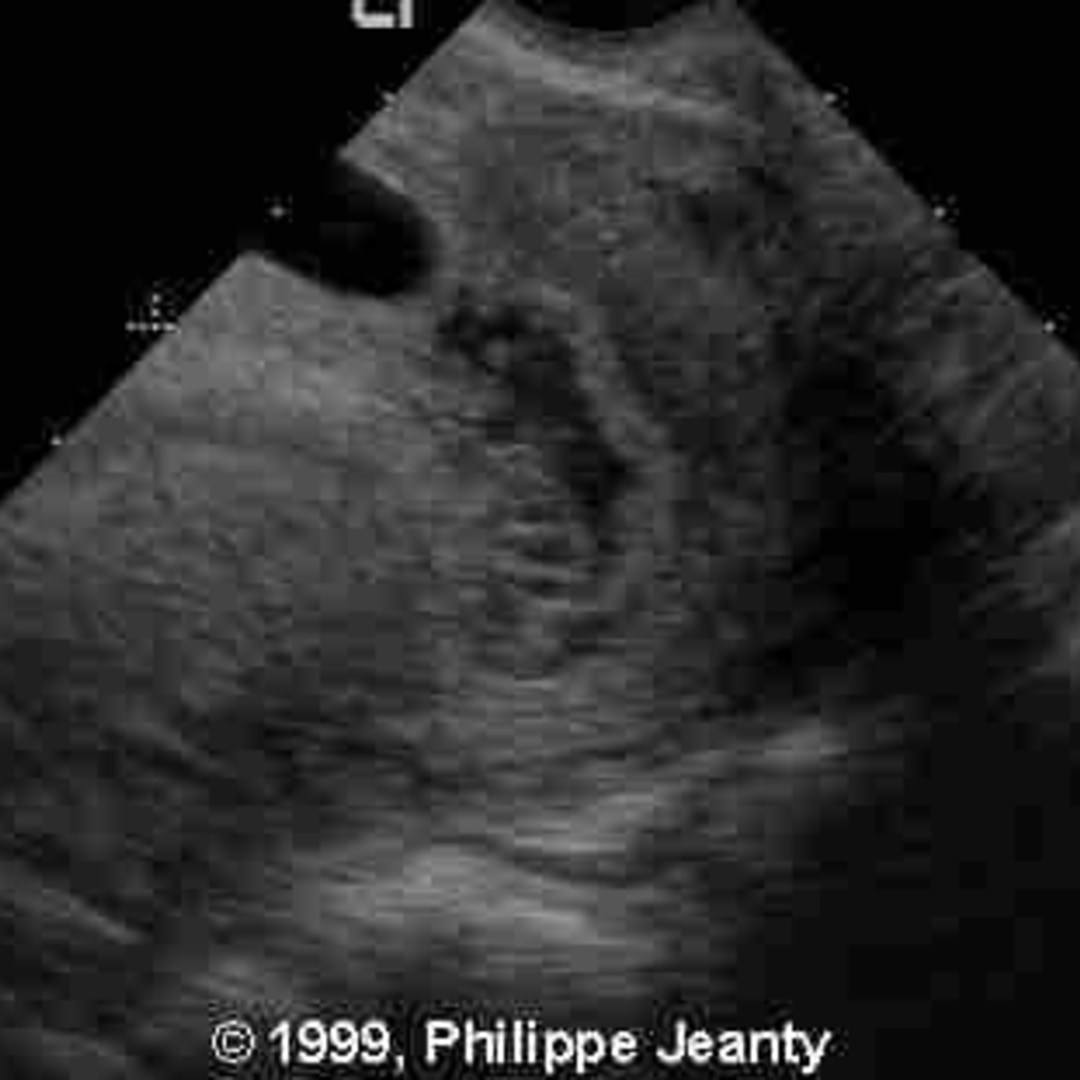

📃 The vanishing twin What Does A Vanishing Twin Look Like On An Ultrasound When the woman returns for her next visit, only one heartbeat can be heard with a doppler. this article will discuss how vanishing twin syndrome is detected on an ultrasound, the symptoms associated with having a. how will i know if i have a vanishing twin? If your first ultrasound identified. Most often, a vanishing twin is diagnosed. What Does A Vanishing Twin Look Like On An Ultrasound.

📃 Vanishing twin What Does A Vanishing Twin Look Like On An Ultrasound since ultrasonography and transvaginal sonography. this article will discuss how vanishing twin syndrome is detected on an ultrasound, the symptoms associated with having a. how will i know if i have a vanishing twin? vanishing twin syndrome (vts) is a miscarriage that causes a pregnancy involving twins to become a. The doctor identifies two fetuses, and. What Does A Vanishing Twin Look Like On An Ultrasound.